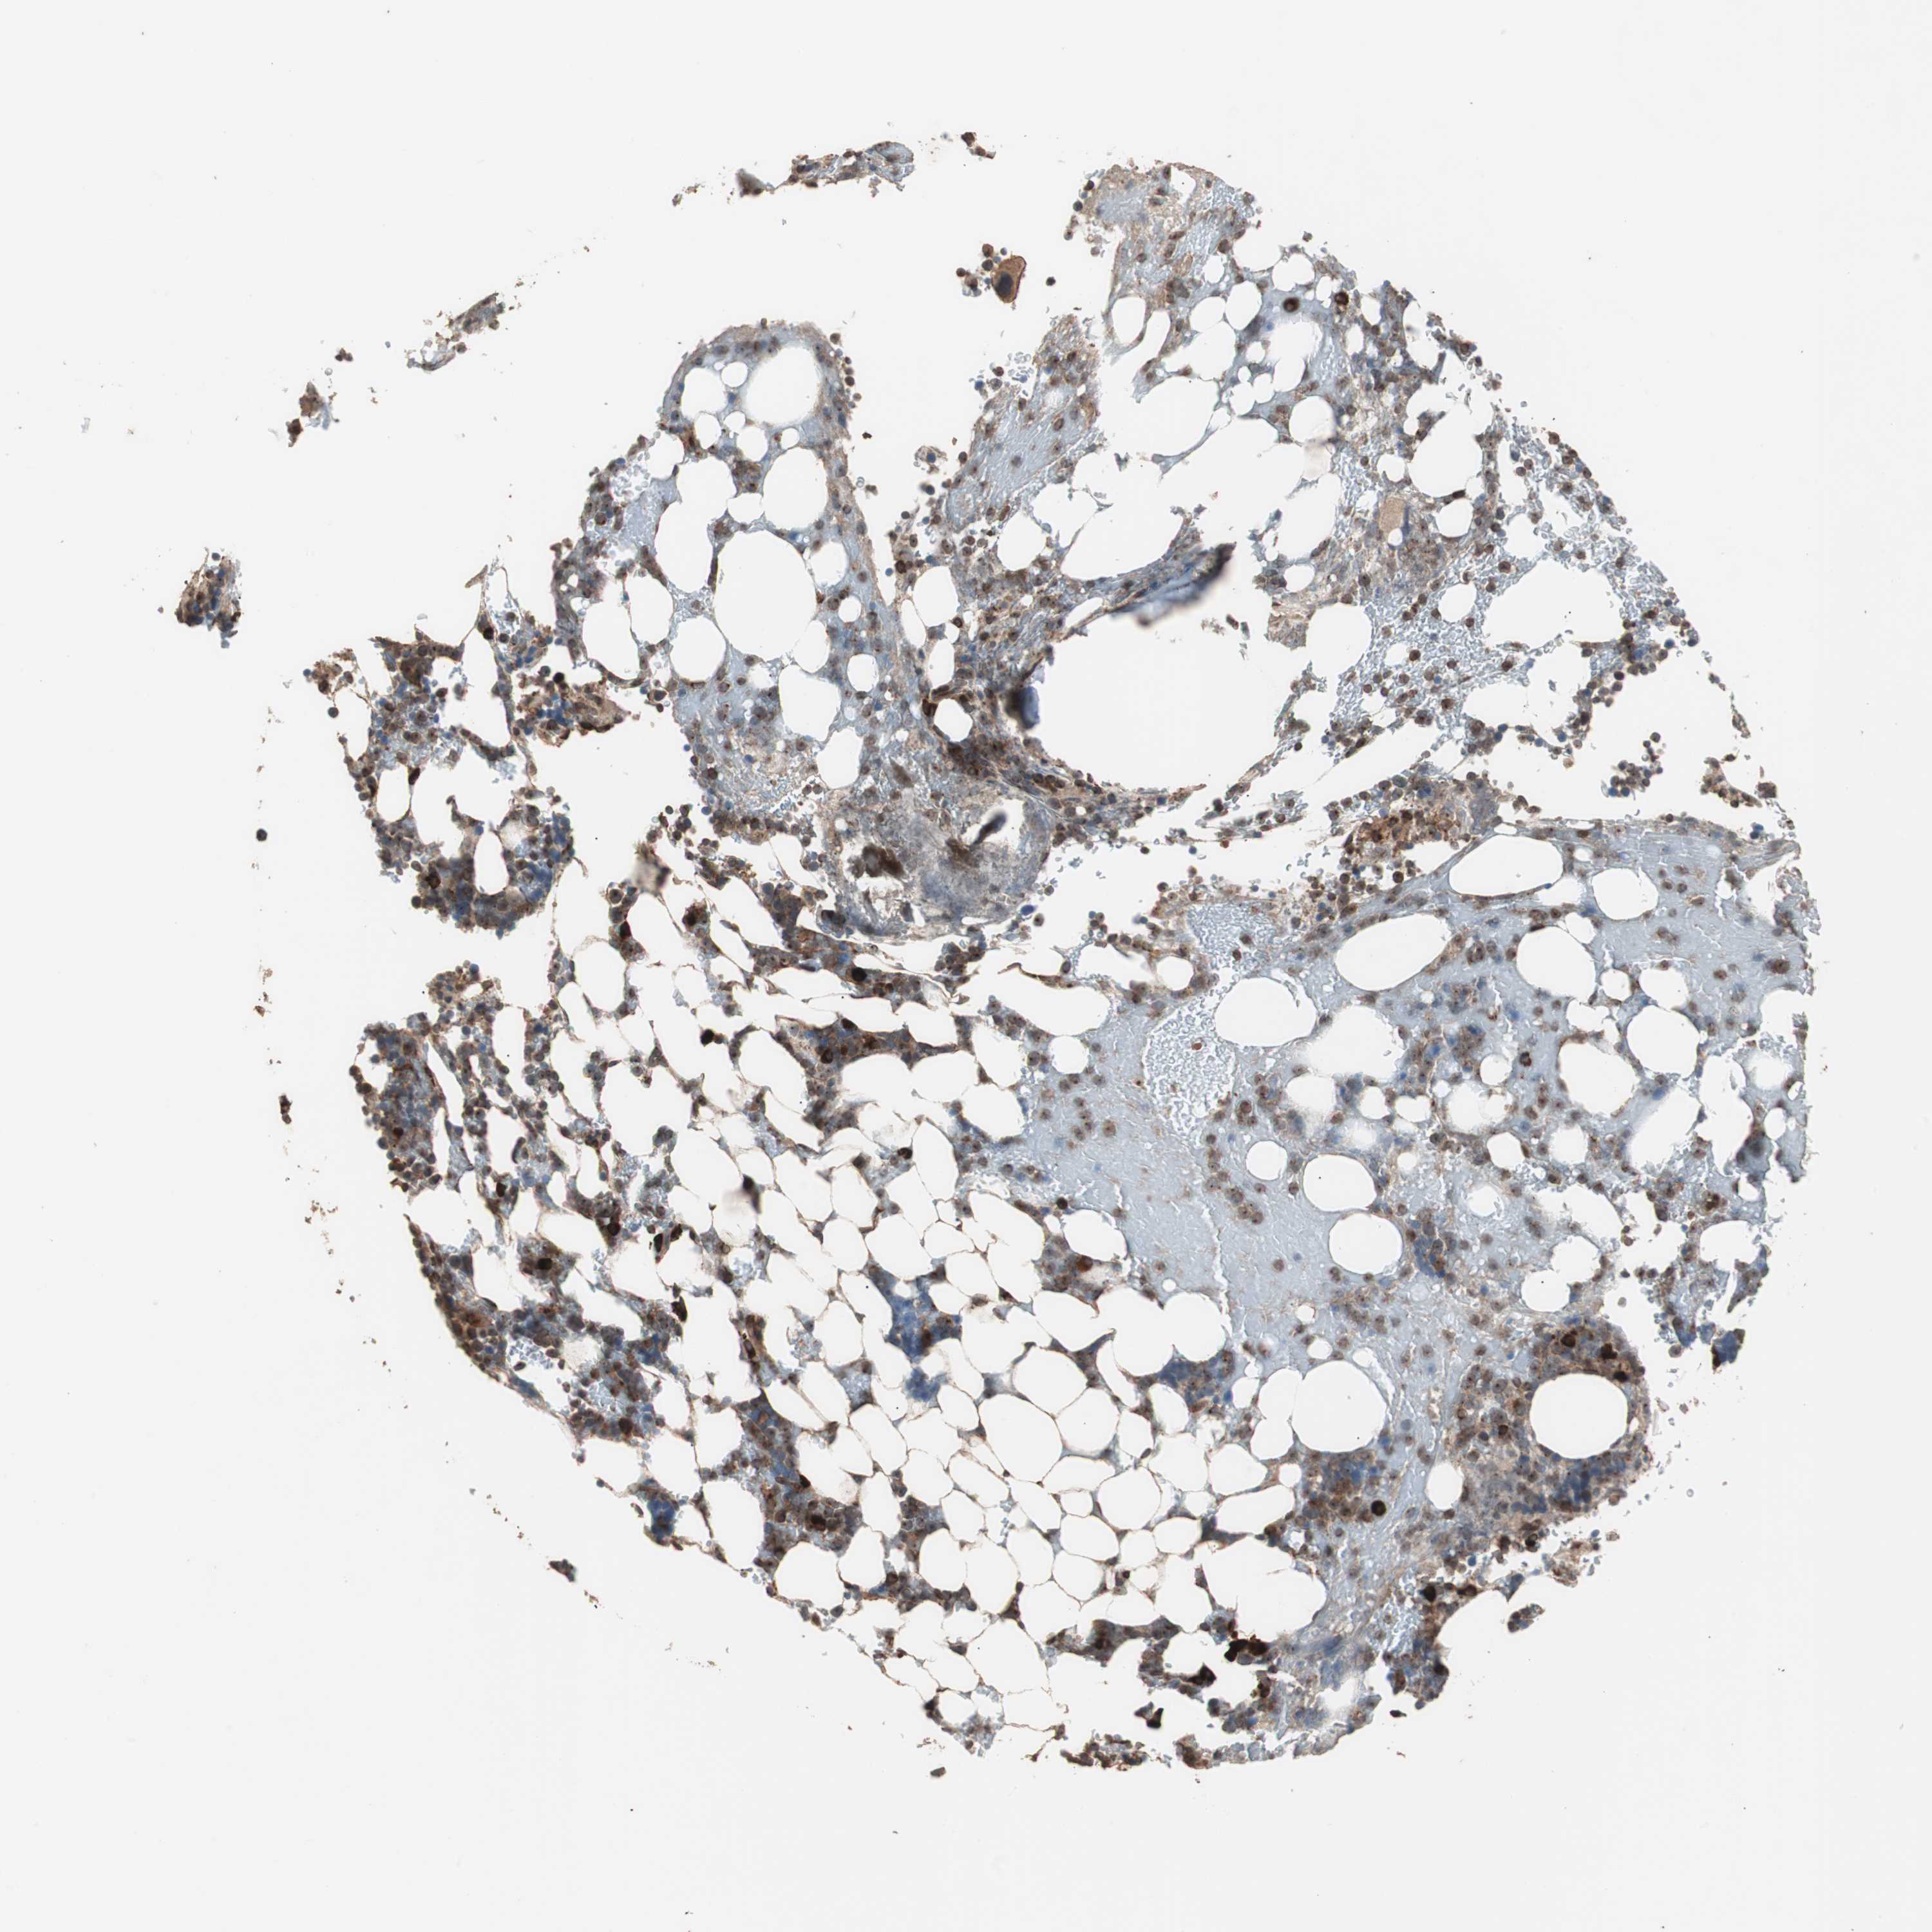

LZTS1